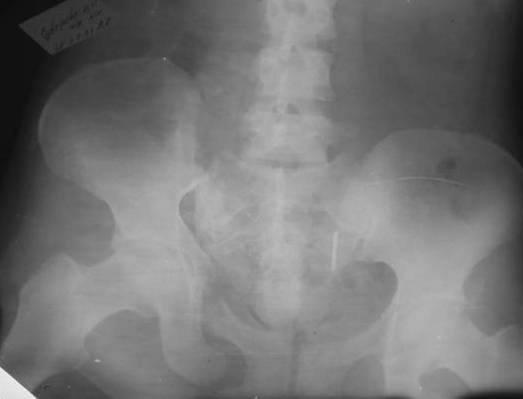

Дорогой Андрей. Мы имеем дело с комбинированной (ротационно и вертикально) нестабильностью таза со смещением правого гнемипелвиса. При таких переломах, фиксация только переднего полукольца вне зависимости от метода фиксации, как уже было сказано Djoldas Kuldjanov, M.D., не может создать адекватной фиксации. И перелом пластины был вполне ожидаемым после активизации пациента. Смещение сохраняется, и по-видимому не 2 см., а все 4, если не более. Разница всего (+2 см) по конечностям как вы указываете, скорее скомпенсировано позвоночником и протезом. Дополнительные снимки или КТ исследование помогли бы уточнить степень смещения с точностью до мм., выявить перелом поперечного отростка пятого поясничного позвонка, или помимо разрыва правого крестцово-подвздошного сочленения выявить перелом боковой массы крестца справа и т.д. При возможности, конечно, все это желательно сделать. Но мало что изменится с практической точки зрения, т.к. задача - это низведение репозиция и надежная фиксация правого гемипелвиса. Учитывая плачевный опыт стержневого аппарата, давность травмы совершенно очевидно, что поставленная задача достижима при открытой репозиции и одномоментной фиксации переднего полукольца с артродезированием правого крестцово-подвздошного сустава. Операция выполняется в положении больного на здоровом боку или полубоку из расширенного трансоссального подвздошно-пахового доступа с переходом на лонное сочленение доступом по Pfannenstiel. Указанный доступ обеспечивает подход к крестцово-подвздошному сочленению как спереди так и сзади. После артродезирования выполняется синтез лонного сочленения. Клинический пример

Пациентка С.26 лет. Травма за 6 месяцев до поступления

Укорочение правой нижней конечности до 10см

23.09.2003. Одновременный остеосинтез переднего и заднего тазовых полуколец

Результат через 10 дней

и 8месяцев после операции